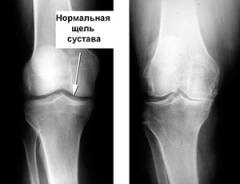

При хроническом течении артрита могут отмечаться изменения на рентгенограмме:

- Околосуставной остеопороз. Участок размягчения костной ткани возле сустава.

- Сужение суставной щели. Уменьшение расстояния между костями из-за отека.

При хроническом артрите на рентгенограммах могут быть выявлены следующие изменения:

- Околосуставной остеопороз. Участки размягченной костной ткани рядом с суставом под хрящом.

- Сужение суставной щели. Уменьшение расстояния между костями из-за воспаления, вызванного отеком хряща.